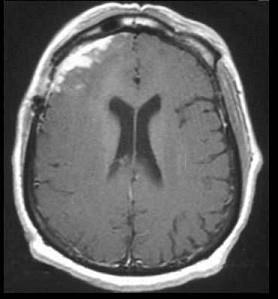

问题 男,16岁,发热、头痛半月,抽搐、意识模糊一天,CT检查如图,最可能的诊断为()

选项 A.脑水肿 B.脑积水 C.脑萎缩 D.结核性脑膜炎 E.结核性脑脓肿

答案 D